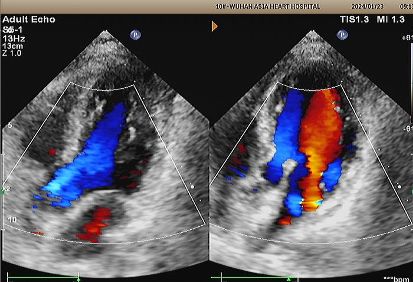

Echo di 1 anno:

No visible disc structures – replaced by 8mm tissue thickening at the septal implant site.

Zero residual shunt (rest or post-Valsalva).

Assorbimento completo del dispositivo confermato.